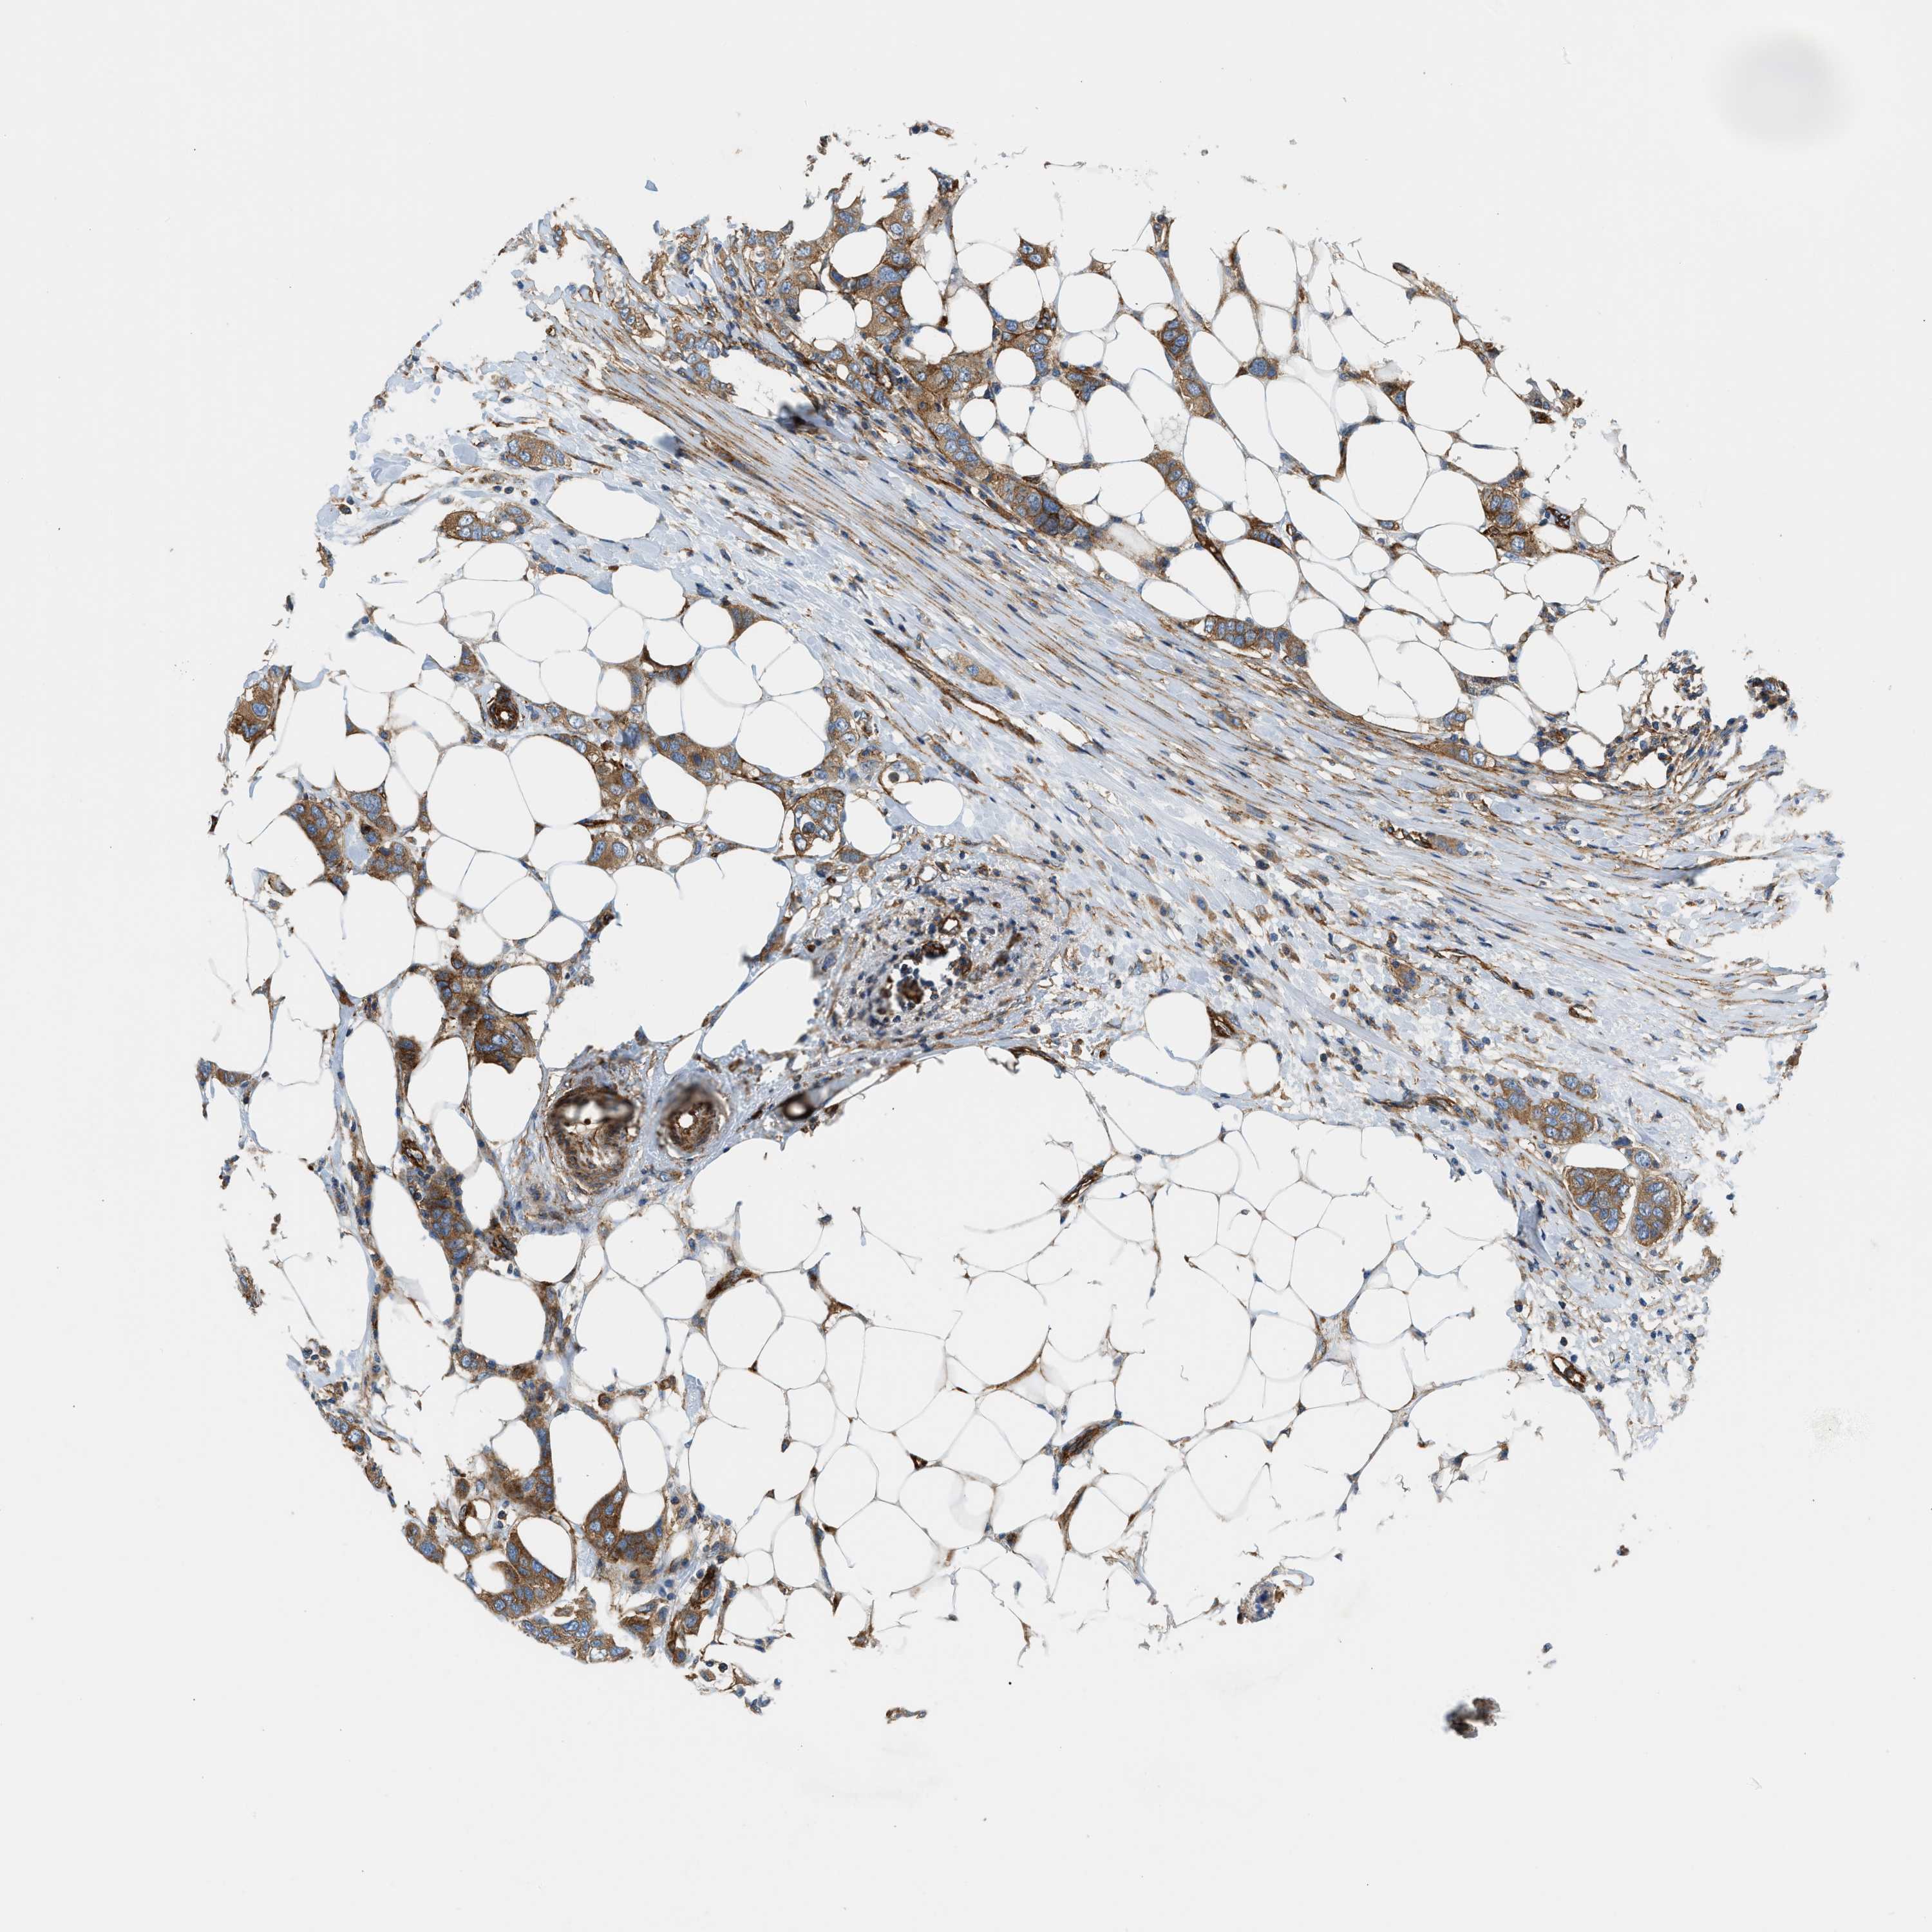

CANCER BREAST CANCER Show tissue menu

BRCA TCGA BRCA VALIDATION PROTEIN EXPRESSION

ANTIBODIES

AND

VALIDATION